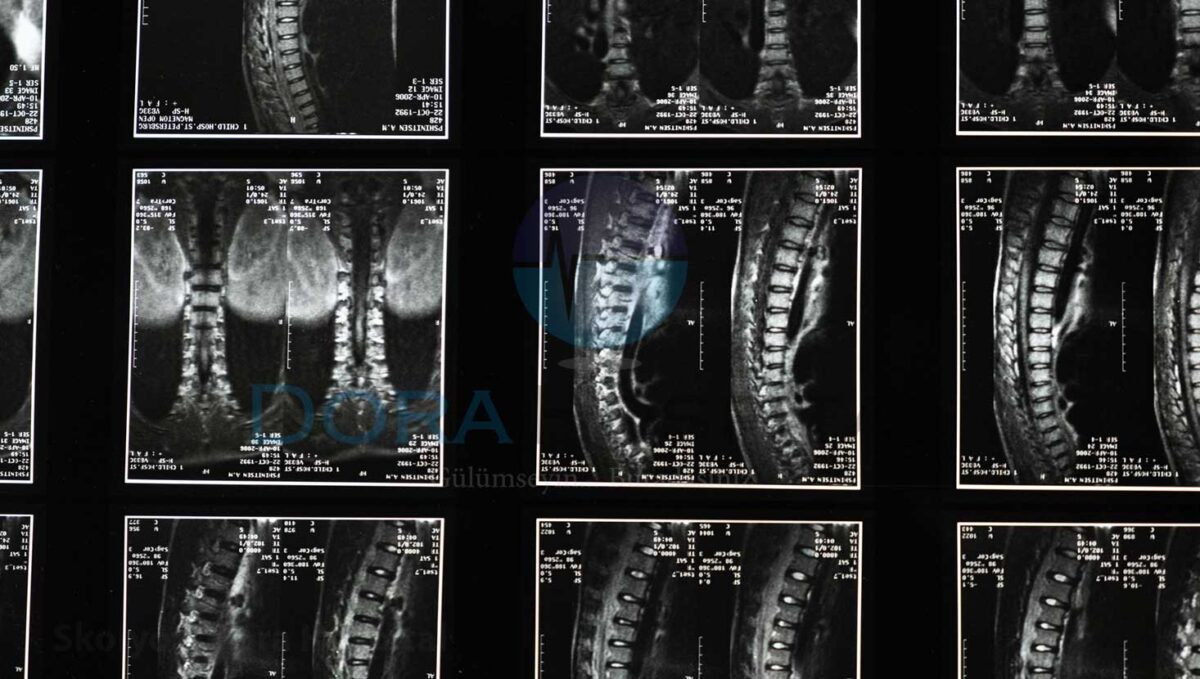

Skolyoz tanısında uzman doktorunuz ilk olarak röntgen filmi çekilmesini isteyecektir. Burada amaç, omurgadaki eğriliği doğrulamak ve nu eğriliğin derecesini ve yerini saptamak olacaktır. Aynı zamanda kişinin kemik yapısına ait kalıtsal bir bozukluk olup olmadığını anlamaya yarayacaktır. Uzman bu süreçte çocuğa 6aylık aralarla röntgen filmi çekilmesini isteyerek skolyozun takibini yapmış olur. Diğer taraftan cerrahi uygulanacak hastalara kemik sintigrafisi, bilgisayarlı tomografi (CT) veya manyetik rezonans (MR) gibi diğer görüntülü tetkiklerin uygulanmasını da isteyebilmektedir. Skolyozda çoğu zaman MR çekimine gerek kalmadan sadece radyolojik tetkikte tanı koyulabilir.

Çekilen tüm görüntülü çekimler skolyozun formunu ve derecesini belirlemek içindir. Skolyoz derecesinde kullanılan en sık yöntem ise Cobb açısıdır. Cobb açısı sayesinde skolyoz takip edilerek kişiye en uygun tedavi yöntemine karar verilir. Cobb açısı alınırken eğilmenin başladığı omurganın üst sınırı ile eğilmenin bitiği omurganın alt sınırından çizilen çizgiler sayesinde ölçüm yapılmaktadır. Bu çizgilere çizilen dikmeler arasındaki açılar eğilme derecesini verecektir.